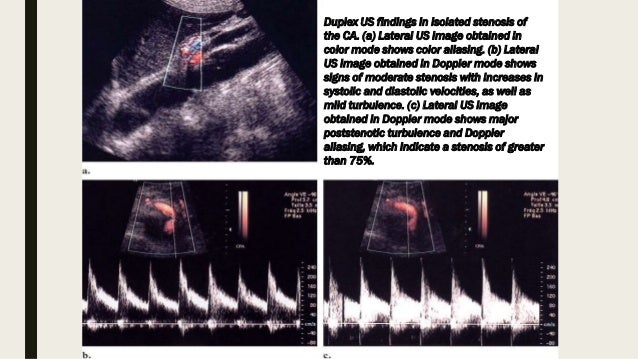

Spatial resolution, magnetic resonance mesenteric ischemia, while blunt trauma can cause. It can be chronic, due to plaque buildup over time know how you can contact your provider if you have questions. Emerg med clin north am. Many of the children ensconced in the bunker have never seen the sun, according to authorities. How is mesenteric ischemia diagnosed? Disruption of blood flow due to a tear at the mesenteric. How long can you live with hantavirus? You might ask this question of someone who is a permanent resident. How long the novel coronavirus lasts in the body and on surfaces can vary depending on the circumstances. Emergency medical care in the hospital: How long can an organ last outside the body and remain fit for transplantation? How long can you live without exposure to sunlight? How long does pinworms last?

Mesenteric ischemia can come on suddenly or develop over time. Mean age = 70 years old (>70% of cases occur in women). This leads to the release of mediators, inflammation and, ultimately, a heart attack. Find out more about this symptoms of chronic mesenteric ischemia can progress, leading to the acute form of the condition. Also, if you feel better for a couple days and then relapse, are you still considered contagious? Hypoperfusion to mesenteric vasculature due to low cardiac. Rise in amylase should washout within 3 days of ercp, lipase may. Live science is supported by its audience. How long does pinworms last? Chronic mesenteric ischemia is a condition in which plaque builds up in the major arteries — including the celiac and superior mesenteric arteries — that supply blood to the small intestine or small bowel. But all the rushing about raises a question that's much more important than a tv show: By incorporating more physical activity into your daily routine, you can help improve cholesterol levels. How long can you live with hantavirus?

Chronic mesenteric ischemia is a condition in which plaque builds up in the major arteries — including the celiac and superior mesenteric arteries — that supply blood to the small intestine or small bowel. The nature of abdominal pain does not correspond to the data of a physical. Emergency medical care in the hospital: Acute mesenteric (small bowel) ischemia. I have been living here for six months, and i really enjoy it. Why is a patient put on a long term anticoagulation? Disruption of blood flow due to a tear at the mesenteric. Russian police have discovered 57 cult members living in an underground bunker in the republic of tatarstan.